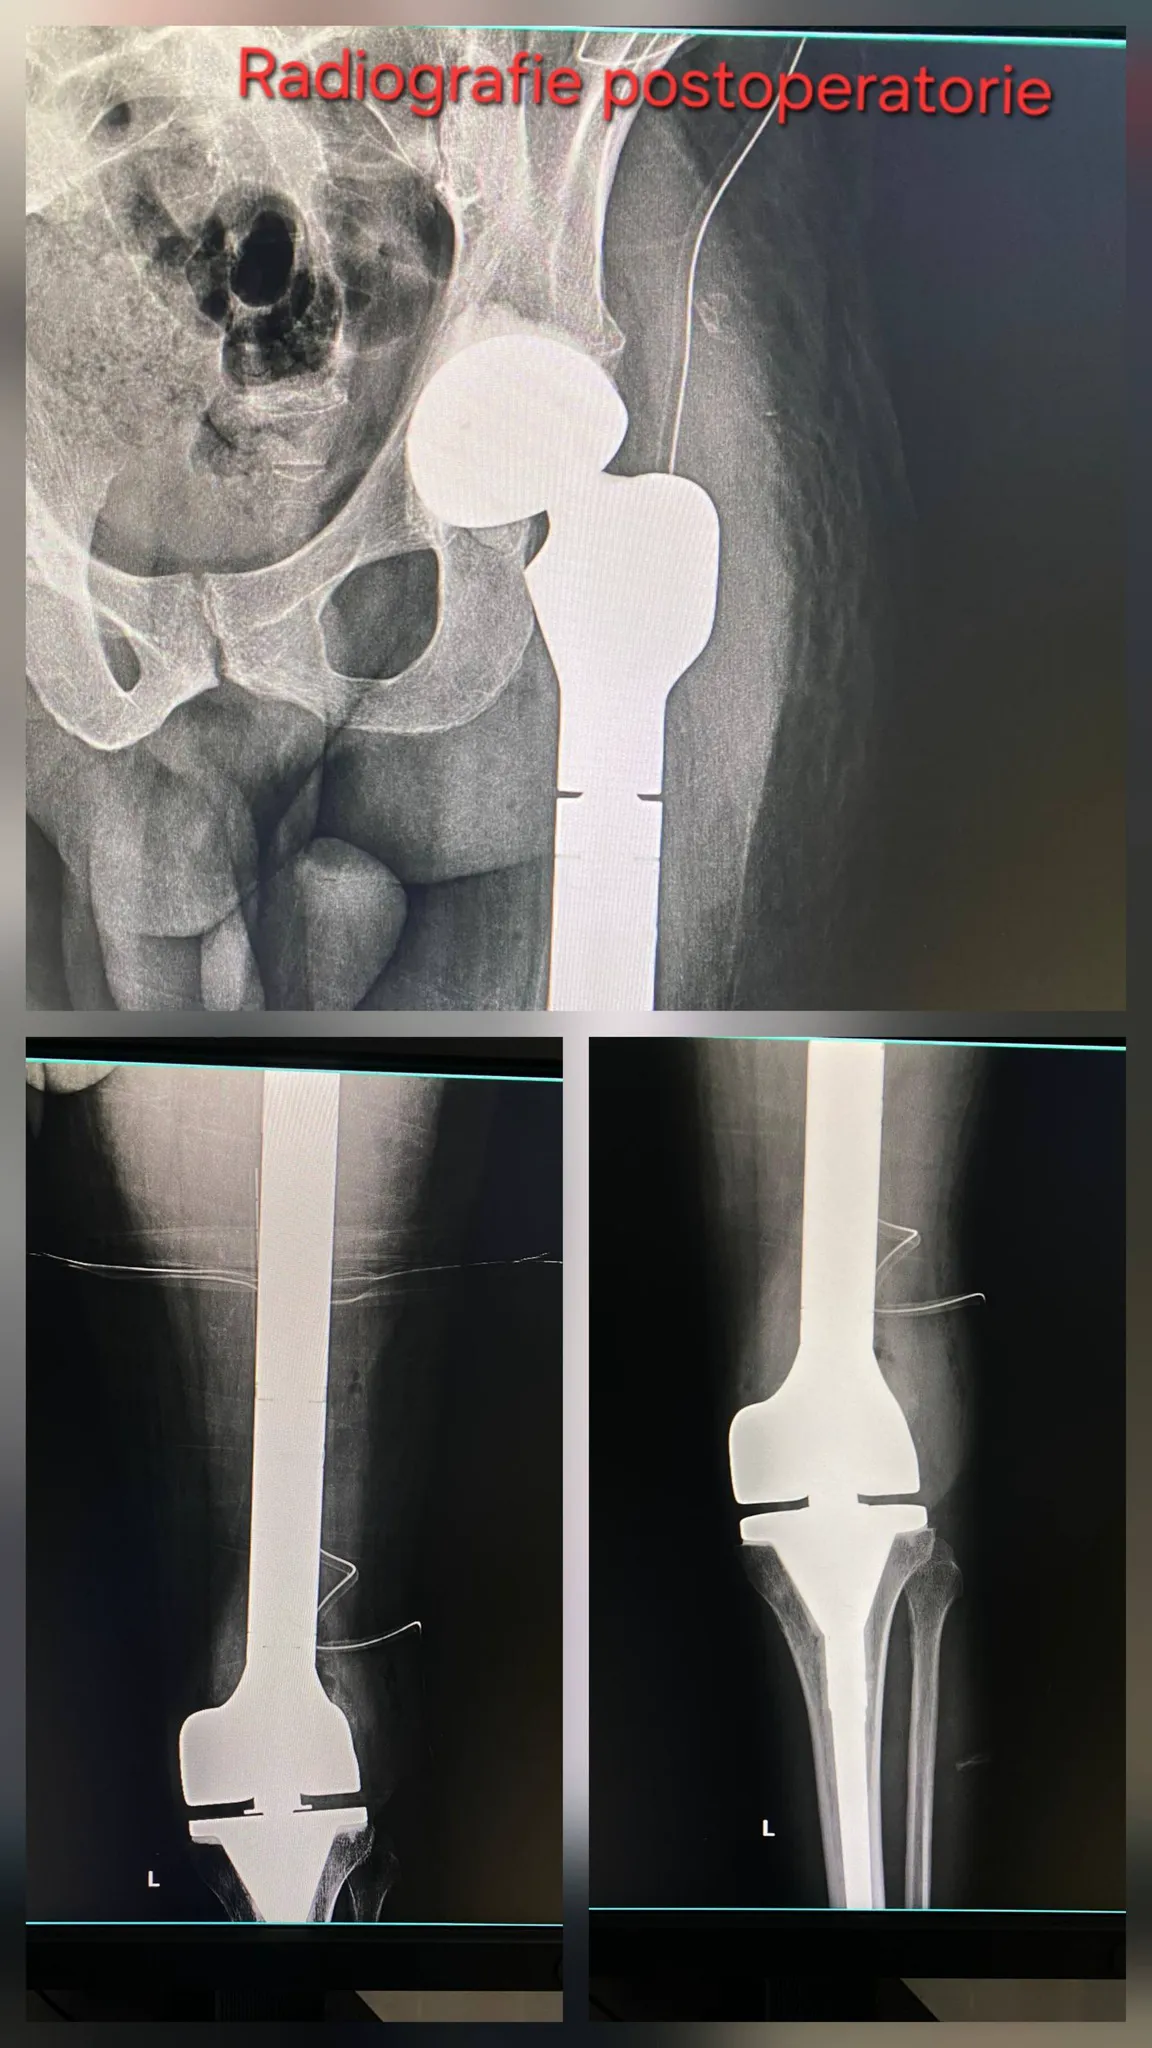

Reușită medicală de excepție la Spitalul Universitar. Echipa condusă de profesorul Cătălin Cîrstoiu a operat un pacient oncologic de 36 de ani

O intervenție chirurgicală extrem de rară și complexă a fost realizată la Spitalul Universitar de Urgență București, unde echipa coordonată de prof. univ. dr. Cătălin Cîrstoiu a reușit rezecția completă a femurului afectat de o patologie tumorală și înlocuirea lui cu o megaproteză, salvând membrul unui pacient oncologic de 36 de ani.

Pacientul, diagnosticat în urmă cu aproximativ trei ani cu displazie fibroasă femurală și ulterior cu chist osos anevrismal, suferise deja o fractură pe os patologic și o artroplastie de șold în străinătate, urmată de complicații și dureri persistente. Din cauza deteriorării extinse a femurului și a riscului ridicat de hemoragie, medicii au efectuat înaintea operației o embolizare vasculară, pentru a reduce sângerarea și a crește șansele de reușită.

Intervenția realizată la SUUB a constat în îndepărtarea completă a femurului grav afectat și reconstrucția membrului inferior cu o megaproteză tumorală personalizată, una dintre cele mai dificile proceduri din ortopedia oncologică. Operația oferă pacientului șansa de a-și păstra piciorul și de a avea o recuperare funcțională semnificativă, ca alternativă la amputare, urmând acum o perioadă de recuperare medicală și monitorizare atentă.

„Recent a fost realizată cu succes cea de-a cincea intervenție chirurgicală de amploare constând în rezecția și înlocuirea completă a femurului cu o megaproteză tumorală.

Cazul este al unui pacient tânăr, în vârstă de 36 de ani, diagnosticat cu displazie fibroasă femurală în urmă cu aproximativ 3 ani, care la scurt timp după diagnostic a suferit o fractură pe os patologic de femur proximal, pentru care s-a intervenit într-un spital regional din Spania și s-a practicat artroplastia totală a șoldului cu o proteză primară. La mai puțin de 1 an post operator pacientul a prezentat din nou dureri cu decimentarea aseptică a implantului. Pacientul a fost internat ulterior în cadrul unui spital județean, unde s-a realizat o biopsie incizională cu stabilirea diagnosticului de chist osos anevrismal. Având în vedere complexitatea cazului, pacientul a fost transferat în secția de ortopedie a Spitalului Universitar de Urgență București.

Preoperator, având în vedere riscul hemoragic crescut, s-a practicat embolizarea principalelor surse vasculare, cu ajutorul medicilor din compartimentul de radiologie intervențională sub coordonarea dr. Bogdan Dorobăț”, se arată în anunțul făcut pe pagina de Facebook a SUUB.

„Intervenția, extrem de complexă, a presupus îndepărtarea integrală a femurului sever afectat de patologia tumorală și reconstrucția membrului inferior prin implantarea unei megaproteze tumorale personalizate. Operația a fost efectuată de o echipă multidisciplinară formată din medici ortopezi, medici anesteziști și personal medical auxiliar, într-un efort coordonat de către Prof. Univ. Dr. Catalin Cîrstoiu.

Această procedură reprezintă una dintre cele mai dificile intervenții din sfera ortopediei oncologice, fiind indicată în cazurile în care tumora afectează extensiv femurul și structurile adiacente și vine în sprijinul pacienților ca alternativă a tratamentelor radicale, precum amputația. Prin utilizarea megaprotezei tumorale, pacientului i se oferă șansa păstrării membrului și a unei recuperări funcționale semnificative.